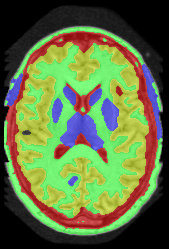

![]() |

||||

| (a) tree and min-margins | ||||

|

Subject 2 |

Subject 3 |

Subject 4 |

| ground truth | a-exp [7, 8] | QPBO [25, 8] | ours | |

Brain Segmentation:

We combined the labeled regions in dataset [19] (T1W MRI) to create the tree shown in Fig. 15(a). In this setting, the data term is the sum of color model penalty and an shape prior [5] based on an automatically extracted brain mask using [16],

| (5) |

where is the intensity at pixel and is the Euclidean Distance Transform of the extracted brain mask. Min-margins are shown in Fig. 15(a). We also added a Hedgehog prior [13] for the sub-cortical grey-matter to help our energy differentiate between grey-matter and sub-cortical grey-matter.

In this application our method outperformed QPBO in most cases and a-exp in all cases. In fact a-exp always converged to a weak local minima in this setting, see Fig. 15. Based on our experience the quality of a-exp result depends on various factors, e.g. tree complexity, the number of min-margins introduced, the order in which labels are expanded, and the initial solution. For the subjects that QPBO was able to find the global optimal Path-Moves either found the global optimal or a very close solution.